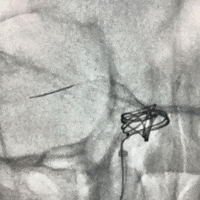

密网支架半释放状态下,沿栓塞微导管顺利填入泰杰Perfiller®栓塞用可膨胀弹簧圈系统 9mm*30cm ,然后撤出栓塞微导管。

完全释放支架后即刻造影,可见支架贴壁良好。